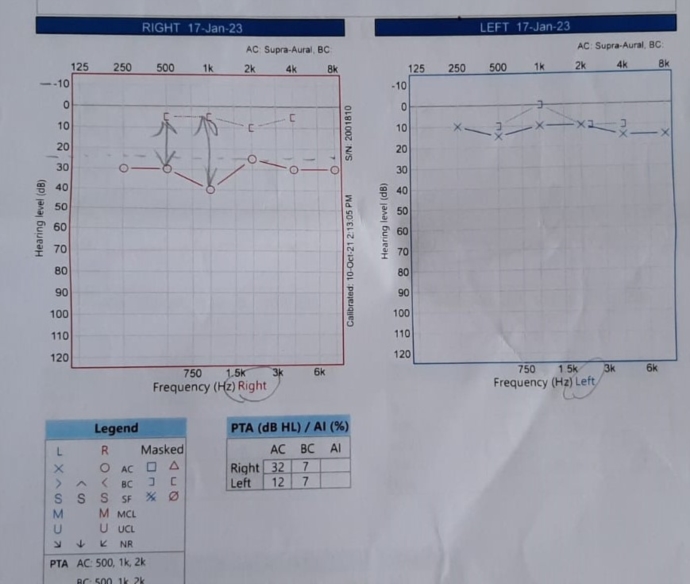

I had a hearing test which showed conductive hearing loss of about 40db around the 1k frequency range (see pictures).

The CT scan report came back saying I had Chronic Otomastoiditus and showed opacification of the Mastoid bone and middle ear space. (See pictures)

I think I can see thickening of the of the right ear drum. But I'm not 100% sure. Maybe any curious radiologists out there can correct me. The right middle ear space is opacified so I find it difficult to see any obvious changes to the ossicular chain.

I was told that it would take a while for the middle ear inflammation to go away (6months to a year!) He also said that my right ear drum was sclerotic and rigid and my hearing would never be the same as my left ear. He said the ossicular chain (stapes,incus,malleaus) was fine and not damaged.

I’m not sure this can be true though as normally Myringosclerosis (ear drum sclerosis) doesn’t effect hearing. Whereas Tympanosclerosis effects the ear drum and ossiclular chain.